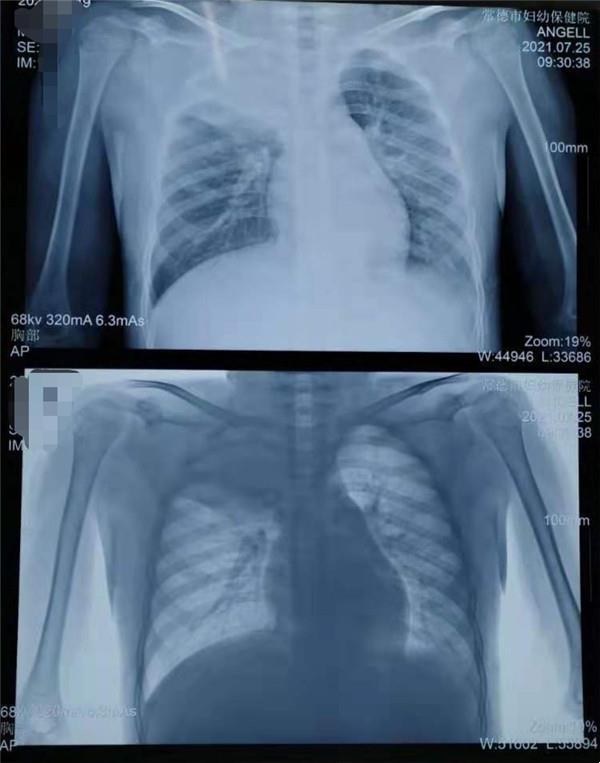

8歲的男孩浩浩(化名),因持續(xù)發(fā)熱、咳嗽,近一個星期也不見好轉(zhuǎn),在家長的帶領下到常德市婦幼保健院兒科就診,擬“社區(qū)獲得性肺炎(重度)”收住院治療,兒科醫(yī)療團隊制定了周密的診療計劃,經(jīng)積極抗感染、化痰止咳、退熱、霧化等處理,浩浩發(fā)燒的癥狀雖有所好轉(zhuǎn),但咳嗽加重,呼吸困難明顯,肺實變加重。

胸部X片:右上肺及左下肺大片高密度影